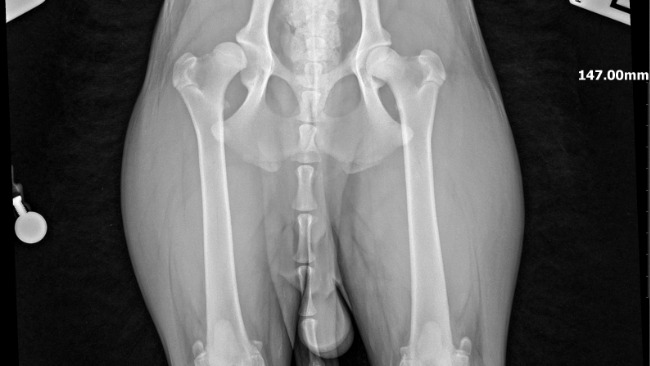

W przychodni zrobiono kontrolne RTG – na szczęście lekarz nas uspokoił. Powiedział, że wszystko wygląda dobrze, kość się goi, nie ma żadnych powikłań i nic nie powinno już boleć 🙏